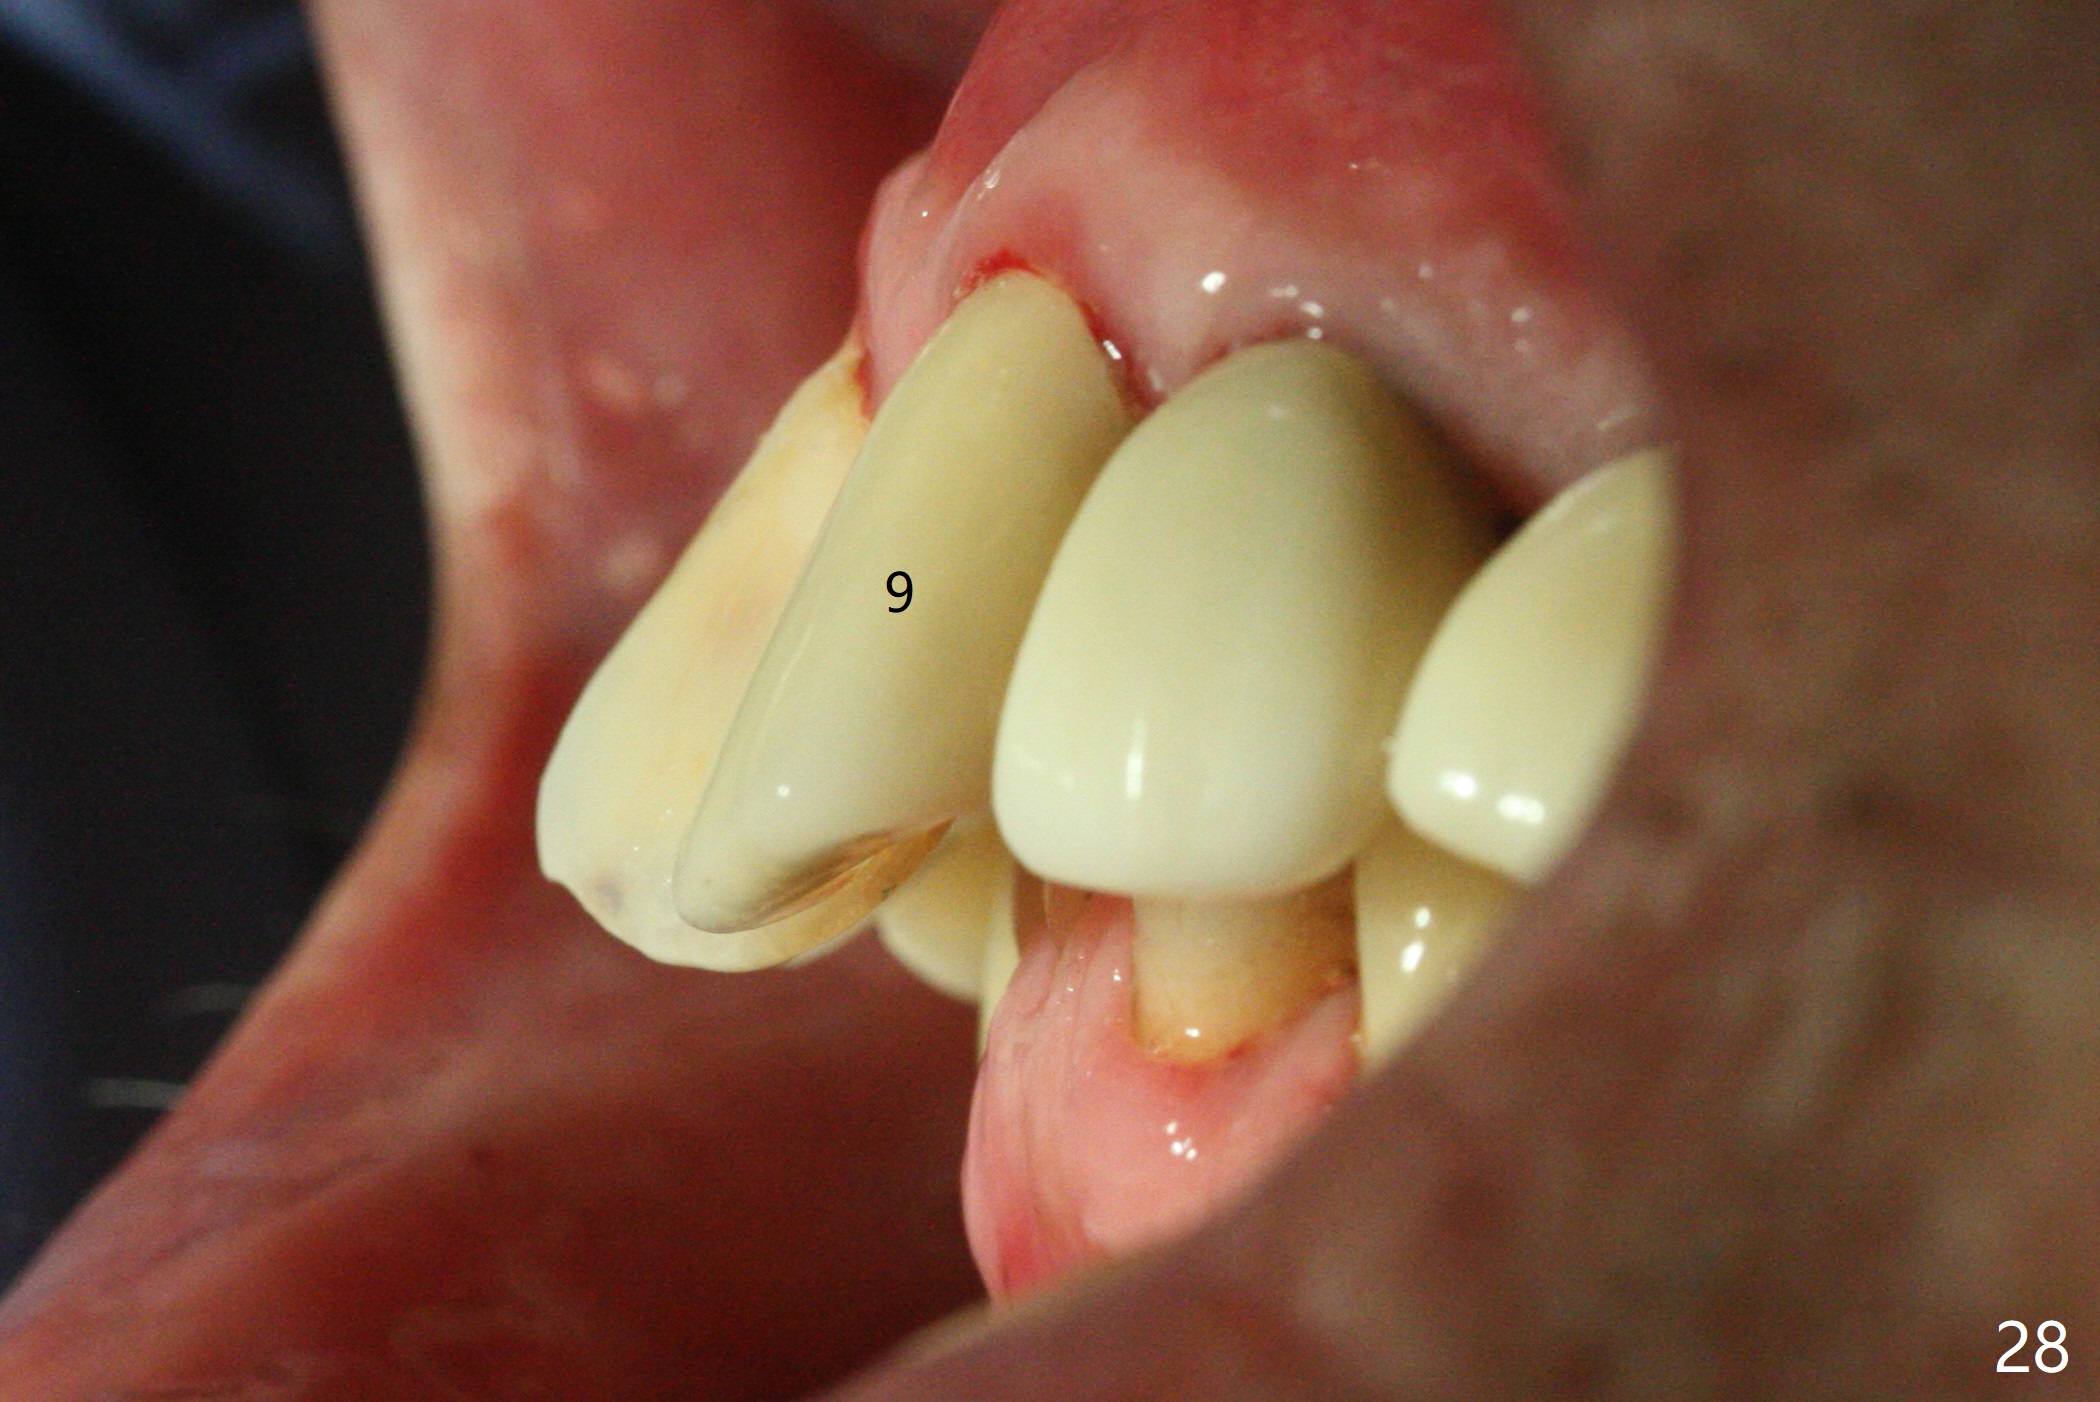

Six months post cementation, the tooth #9 becomes symptomatic.  Is it possible that the implant at #10 is too close to the root of #9?  It is asymptomatic after pulpotomy, but the tooth fractures equi/supragingivally.  Two PAs taken while RCT show osteointegration at #10-12 (Fig.18,19).  While the bone density increases at #10 regular implant, there is minimal bone loss around the 1-piece implants 13 months post cementation (18 months postop, Fig.20,21).  The gingiva remains healthy 19 months post cementation (Fig.22).  76岁病人突然打电话说一个植牙牙冠松动,其实9号牙(自然牙)折裂,6,10-13号牙植牙好像没有骨质吸收(图二十三至二十五),10-13牙位牙龈健康(图二十六,行使功能五年)。9号牙牙冠重新粘固后,显示前牙深覆合,深覆盖(图二十七,二十八)。如果再次脱落需要植牙,选择一段式有助于植入和修复,因为植体和基台直径小。两段式植牙相对基台直径至少4,或者4.5毫米,前牙修复显得笨重。由于9,10牙根和植体接近,9号牙植体需要偏小而长,3x14或者15毫米(图二十九)。